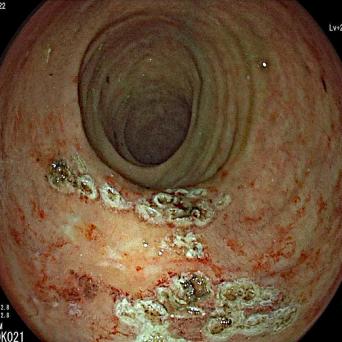

Le dépistage organisé du cancer colorectal s’adresse aux femmes et hommes de 50 à 74 ans inclus à risque moyen de développer ce type de cancer et repose sur un test immunologique simple, rapide, indolore et à réaliser chez soi, permettant de rechercher un saignement occulte dans les selles. Ce test,...

- Cancer colorectal : facteurs de risque et de protection prouvés

- Antécédent familial de cancer colorectal : qui, quand et comment dépister ?

- Cancer colorectal : l’activité physique réduirait la mortalité de 37 %

- Quand et comment prescrire une recherche de sang dans les selles ?

- C’est prouvé : le calcium protège contre le cancer colorectal